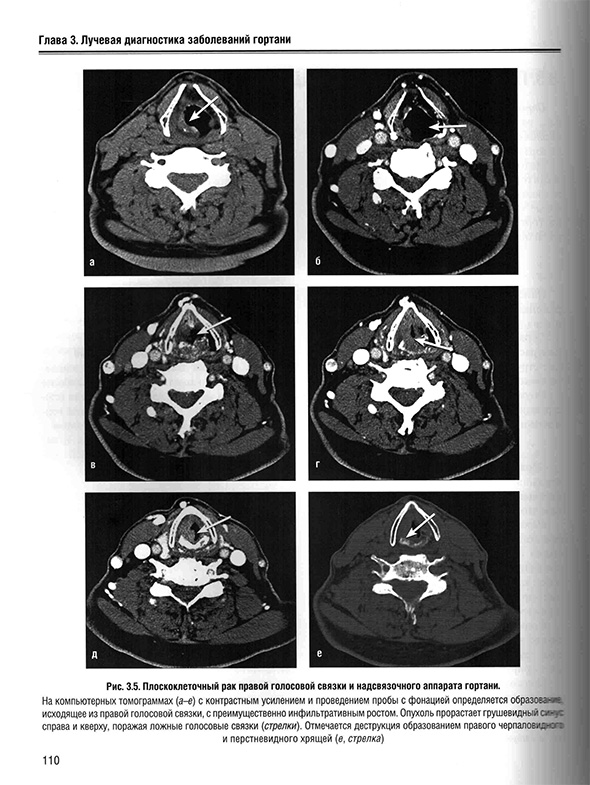

3.4. Плоскоклеточный рак голосового аппарата гортани